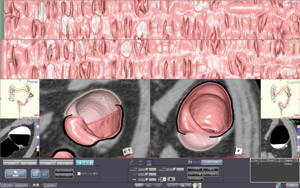

「ziostation2」の大腸解析ソフトウェアは、当センターとザイオソフト社が共同で開発を進めてきました。中でも、画像表示法の1つである仮想展開画像(Virtual Gross Pathology:VGP)に重点をおいてきました。VGPでは、腸管内腔面を1画面に表示できるため、従来の仮想内視鏡(VE)像と比べてきわめて効率的に大腸全体の観察が可能です。大腸には屈曲やヒダが多く、画像の歪みが生じやすいため、それが診断において問題となります。しかし、ziostation2では歪みが最小限に抑えられ、またここ1〜2年で画質も飛躍的に改善されました。結腸紐や半月ひだ、ハウストラなどの描出の進歩は著しく、VE像により即した状態で観察可能であり、ziostation2は臨床的に高いレベルに仕上がっています。

また、画像処理のプロセスも大幅に改良され、ストレスなく高速に各画像表示法を活用できるようになった点も、非常に大きな進歩です。CTCの診断にあたっては、VGPのほか、魚眼方式で観察することができるVEスコープビュー表示、air enema表示などを使用しますが、これらをいかに組み合わせて読影するかが重要なポイントとなります。われわれも当初は、1症例あたりの読影に約30分かかっていましたが、VGPに慣れるに従って診断効率がどんどん向上し、現在では10分程度にまで短縮しています。スクリーニングでは、術前診断と異なり、いかに正確に病変を拾い上げ、存在診断を行うかが重要になりますので、粘膜面全体を一瞬で観察できるVGPはきわめて有用です。

ziostation2では、VGP、VE像、air enema像がすべてリンクしているため、VGPで病変が疑われる部位を画面上でクリックすれば、ほかの画像の同じ部位に印が表示されます。VE像とMPR像との合成画像の質も非常に高く、VGPで印をつけた部位を断層像で詳細に評価することも可能です。当センターでは、実際にこのような診断プロセスを構築することで、読影時間の短縮につながりました。将来的にはVGPを中心に、1症例あたり数分で診断できる診断プロトコルを構築したいと考えています。